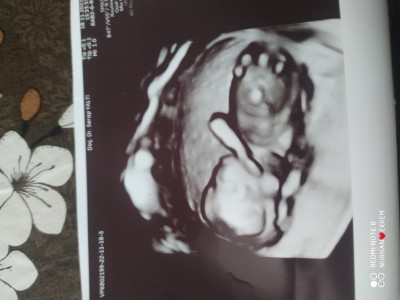

Merhaba arkadaşlar öncelikle herşeyden önce sağlıklı olmaması yetiyor bize ama 7 yıl bekledim merakta ediyorum acaba tahmin ede bilir misiniz 13+2 olduk ama doktor iki hafta sonra gel dedi

Pek anlamam ama aklımdan erkek geçti

Erkek gibi hissediyorum

Bende kız diyorum,ben 12 haftada cinsiyeti öğrenmiştim canım aslında özelde ogrenirsin

Bende kız hissettim

Erkek gibi görünüyor yapısı